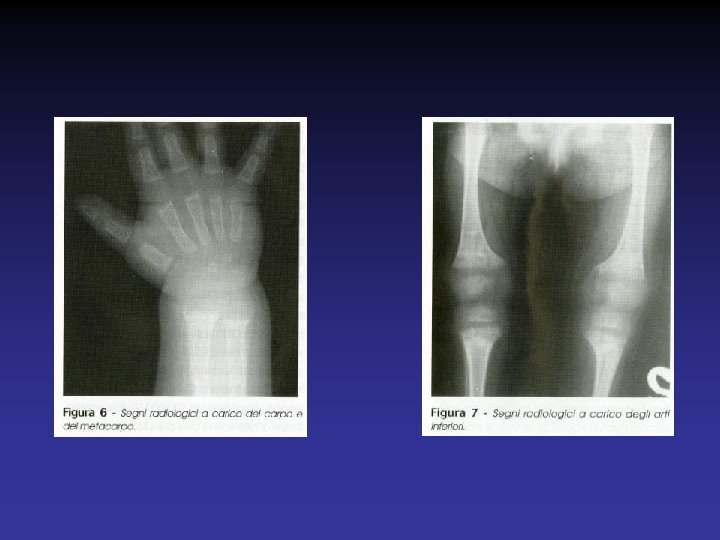

SEGNI RADIOLOGICI DEL RACHITISMO Ø Osteopenia Ø Slargamento, sfrangiamento e deformità “a coppa” delle metafisi Ø Assottigliamento degli spessori corticali Ø Fratture da stress meccanico

MANIFESTAZIONI OSSEE DEL RACHITISMO Ø CRANIO Cranio tabe (consistenza elastica, cedevole delle ossa occipitali e parietali) Caput quadratum (prominenza bozze frontali) Fontanella anteriore ampia Ø TORACE Pectus carinatum o Torace a piccione Solco di Harrison Rosario rachitico Ø ARTI INFERIORI: varismo, caviglia rachitica Ø ARTI SUPERIORI: braccialetto rachitico Ø Ritardo eruzione dentaria, ipoplasia dello smalto Ø Rachide : lieve scoliosi; Cifosi dorso-lombare